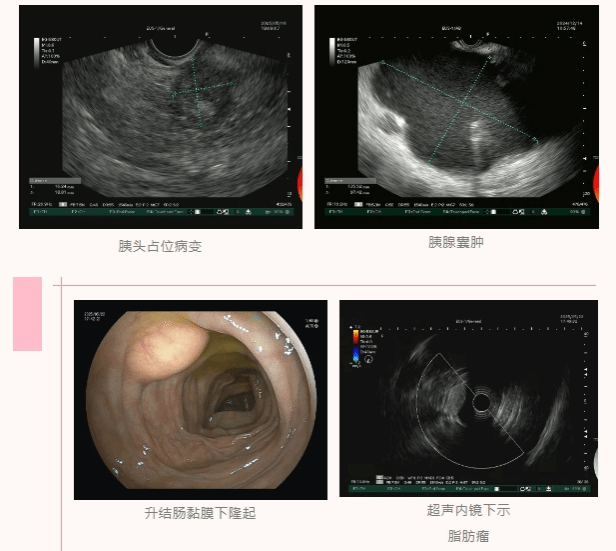

近日,一名中年男性因腹痛前往广医四院肝胆外科就诊,核磁共振检查显示其肝内外胆管扩张,胰腺头部疑似存在肿瘤样改变。由于胰腺位于腹膜后,虽核磁共振提示胰腺头部有占位性病变,但受胃肠道气体等因素干扰,想通过无创方式明确病变性质难度极大。

秉持谨慎手术的原则,肝胆外科医生建议进一步明确诊断——获取被誉为肿瘤诊断“金标准”的病理结果。经MDT多学科会诊讨论后,消化内镜中心团队决定为患者开展超声内镜引导下细针穿刺活检。

5月16日,消化内镜中心团队为患者实施无痛超声内镜检查,精准辨认病灶、瞄准目标,顺利完成胰腺头部病变的超声内镜引导下细针穿刺活检。整个操作一气呵成,患者全程无痛苦,麻醉复苏后也未出现任何不适,对治疗过程十分满意。